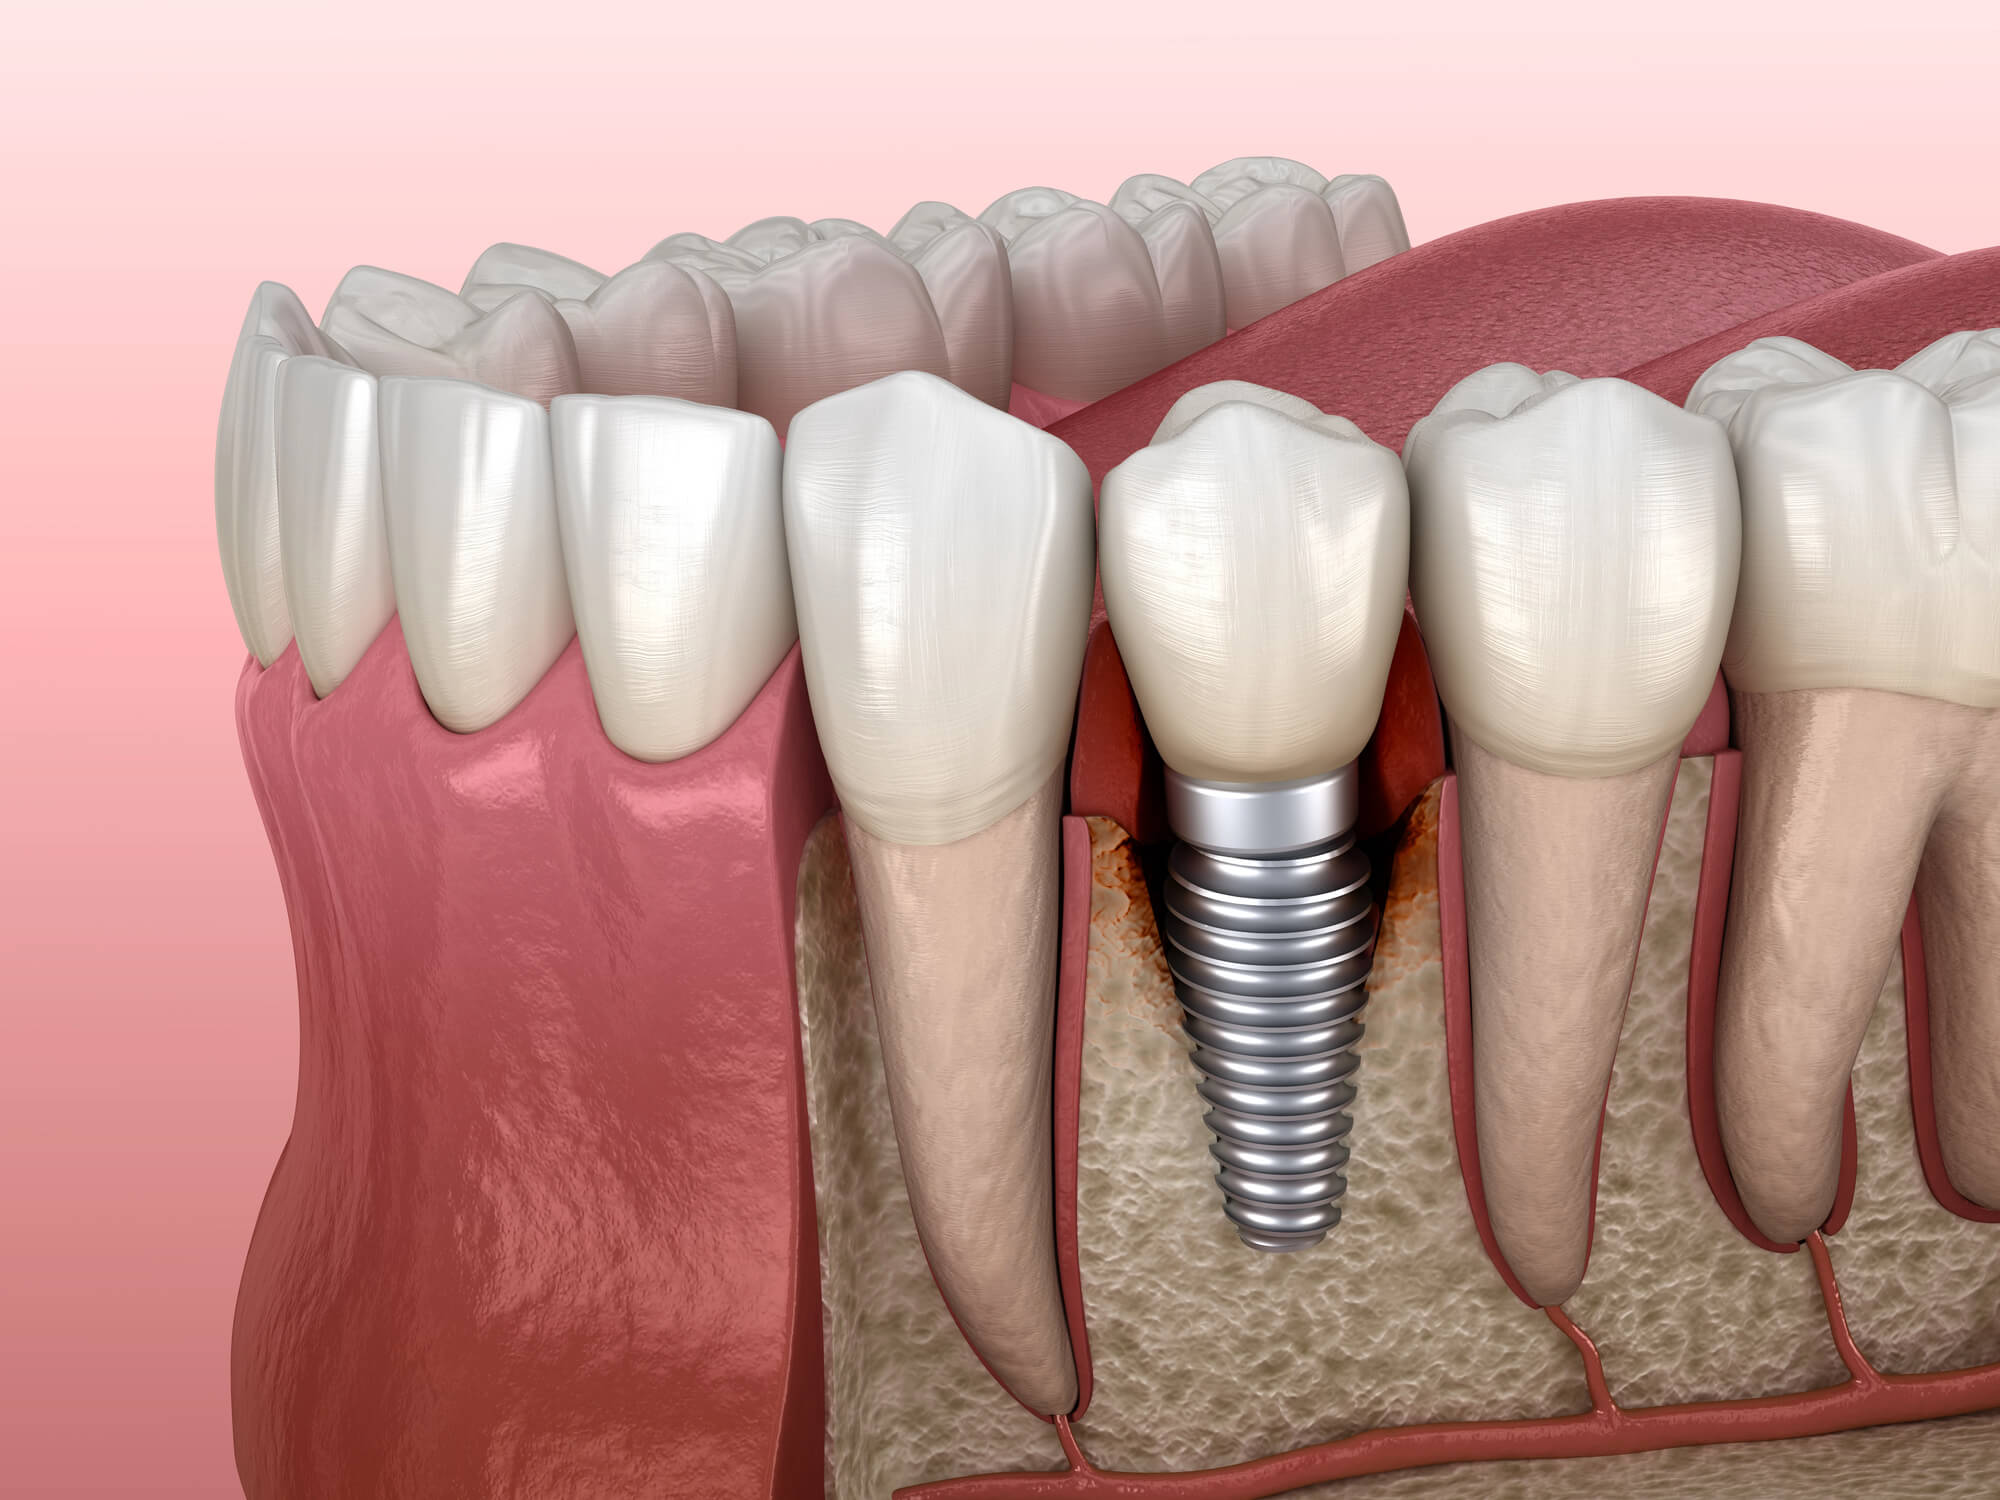

Modern dental implants are one of the most effective, durable, and natural-looking options for replacing missing teeth. Designed to mimic the structure of natural teeth, implants typically consist of a titanium screw or titanium alloy post embedded into the jawbone, topped with an abutment and crown. When placed properly and maintained through regular dental care, implant success rates exceed 95% and up to 99% at 4M.

Following dental implant surgery, it’s normal to experience some faint initial pain or soreness, mild swelling, and light bleeding for the first few days. This is your body’s immune system responding to the procedure and beginning the healing process. As the titanium post integrates with the healthy bone through osseointegration, the implant becomes stable, and symptoms should gradually subside.

4. Gum Recession or Visible Threads

Gum tissue should form a tight, healthy seal around the implant. If the gums begin to pull away, or if you see any exposed metal at the gumline, it’s time to call your dentist.

Indicators of gum recession:

- Visible threads or edges of the titanium implant

- The tooth appears longer or uneven

- Increased sensitivity along the gumline

Recession may result from inflammation, bone loss, or prosthetic misalignment and should be treated quickly to prevent deeper issues or dental implant failure.